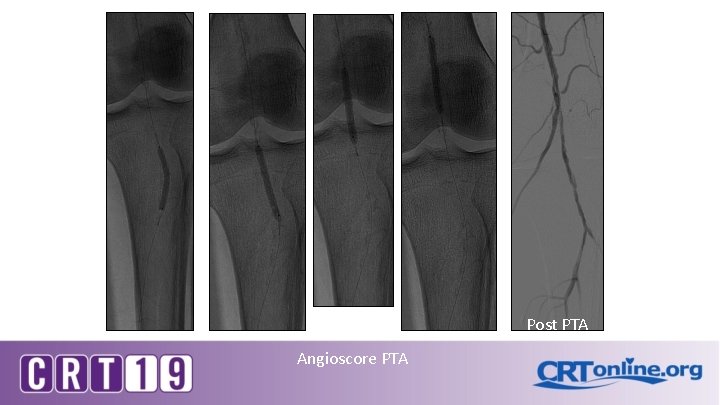

Post PTA Angioscore PTA